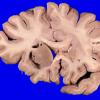

Artifact - Swiss Cheese Brain (3)